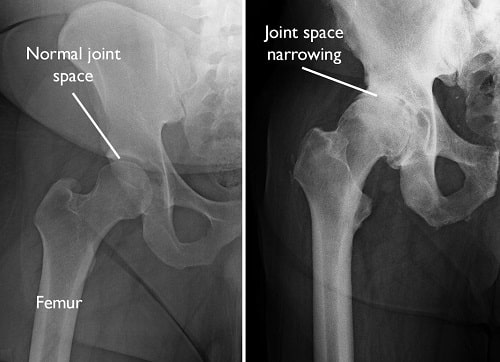

Osteoarthritis (OA) is the most common form of arthritis and a leading cause of joint pain and disability worldwide. It is a degenerative joint disease in which the protective cartilage cushioning the ends of bones gradually wears away. As cartilage deteriorates, bones begin to rub against each other, causing pain, stiffness, swelling, and reduced mobility.

3. Hip Osteoarthritis Bracing

Although less common than knee bracing, hip orthoses can provide stability and pain relief in selected cases.

Certified orthotists assess leg length discrepancy, pelvic tilt, and gait asymmetry before designing a hip support device.